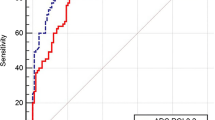

For all the analyzed lymph nodes, the AUC derived from the ROC curves were 0.890 (95% CI: 0.826–0.954) for T2 value, 0.711 (95% CI: 0.613–0.809) for T1SD, and 0.660 (95% CI: 0.562–0.758) for ADC (Fig. 6). T2 demonstrated significantly better diagnostic performance in discriminating between metastatic and non-metastatic lymph nodes compared to ADC (p < 0.001) and T1SD (p = 0.007). The optimal cutoff value for T2 was determined to be 88 ms, resulting in a sensitivity of 84.4% and specificity of 86.7% for nodal metastasis detection. When combining multiple parameters (T2, T1SD, ADC, and short-axis diameter), the AUC increased to 0.929 (95% CI: 0.875–0.983), slightly higher than using the T2 value alone, although the difference was not significant (p = 0.089).

Receiver operating characteristic (ROC) curves for discriminating metastatic from non-metastatic lymph nodes for T1SD, T2, ADC, and a combined model. The area under the ROC curve (AUC) of the T2 value was significantly higher than for the ADC value (AUC T2 value = 0.890, AUC ADC value = 0.660, p < 0.001)

We further examined the diagnostic performance of T1 and T2 mapping in differentiating benign or malignant subcentimeter lymph nodes and non-necrotic lymph nodes within our cohorts. For the 88 subcentimeter lymph nodes, the AUC derived from the ROC curves was 0.918 (95% CI: 0.848–0.987) for T2 value, 0.655 (95% CI: 0.505–0.806) for T1SD, and 0.711 (95% CI: 0.604–0.817) for ADC, with the AUC of T2 value significantly higher than that of ADC value and T1SD (both p = 0.002). For the 107 lymph nodes without nodal necrosis, the AUC derived from the ROC curves was 0.948 (95% CI: 0.907–0.989) for T2 value, 0.694 (95% CI: 0.574–0.815) for T1SD, and 0.666 (95% CI: 0.560–0.772) for ADC, with the AUC of T2 value significantly higher than that of ADC value and T1SD (both p = 0.002).